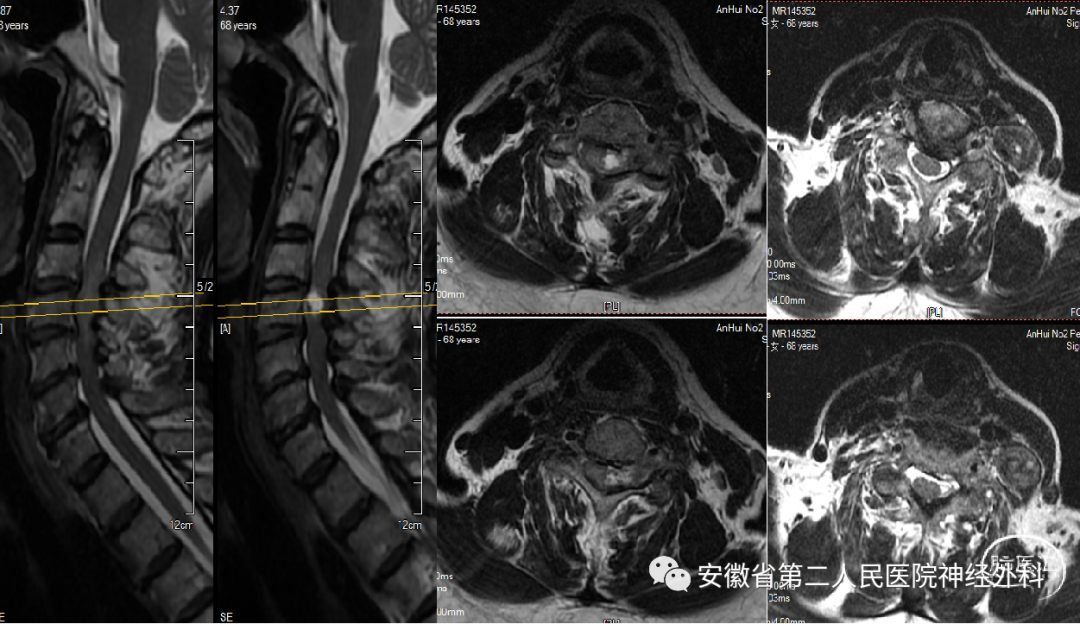

C4水平椎管内外“哑铃型”肿瘤

患者缘于2022年3月份无明显诱因下出现左侧手脚无力,走路不稳,同时伴有左侧肢体麻木感,就诊我科门诊后给予收治入科。体格检查:神志清楚,左侧肢体近端肌力约IV级,远端肢体肌力II-III级,右侧肢体肌力V-级。

术前MRI

患者肿瘤位于高颈段肿瘤,分型为IIb,起源于椎管内神经根并向外生长,手术风险和难度较高,同时合并多阶段颈椎椎间盘突出,术前讨论:考虑同时处理肿瘤和多阶段椎间盘,手术时间长、创伤大、风险高,本次手术拟定先行切除肿瘤+椎板减压,后期视病情行二期颈椎间盘突出手术,手术方案拟在神经电生理监测下经颈前外侧椎间孔入路+备后正中半椎板联合入路切除肿瘤。